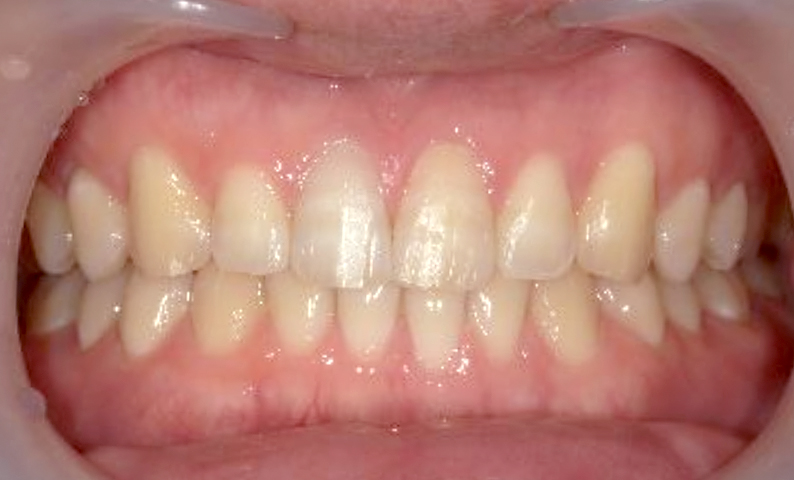

| 治療前 | 治療後 |

|---|---|

|